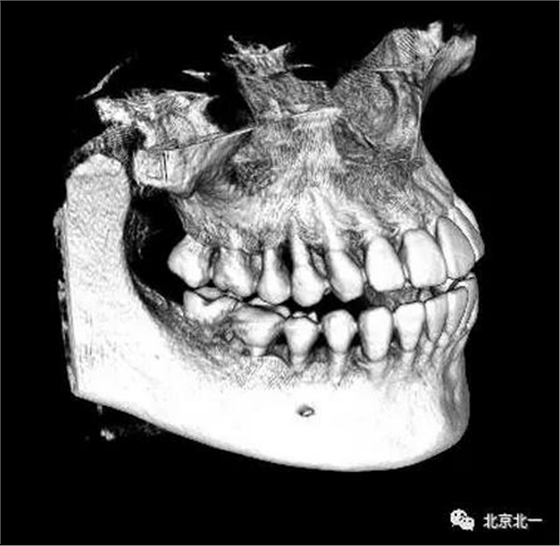

圖四:三維重建

圖五:三維重建可見牙冠突破舌側

總結:單純拍片看牙齒并不復雜, 通過微創(chuàng)拔牙有絲分裂可以避免傷及神經, 本病例特殊之處在于牙齒顏色和骨顏色無法區(qū)別。導致去骨或者分牙比較茫然, 不可大意,以及磨牙的手感和去骨的手感一致時,兩者不好區(qū)分。 只能偏向保守, 多角度拍片再三確認后予以安全拔除。 另外CBCT模式上看智齒位置也有誤差,醫(yī)師要根據經驗調整,特別是在這種哪里是骨,哪里是牙的情況,不能盲目大范圍去骨導致術中骨折。